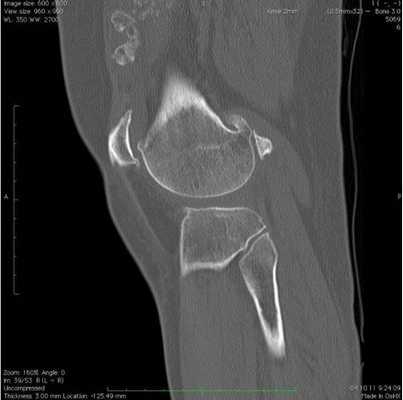

КТ коленного сустава - все что нужно знать

Коленные суставы регулярно испытывают различные воздействия. На их состоянии отрицательно сказываются физические нагрузки, травматические повреждения, переохлаждения, инфекции, возрастные перестройки в организме. Появляются боли, хруст, тугоподвижность и другие неприятные симптомы, заставляющие человека обратиться к врачу. Для постановки диагноза, специалист может назначить КТ коленного сустава. Сканирование на компьютерном томографе позволяет получить детализированные послойные снимки, на основе которых делают выводы о наличии или отсутствии патологии.

Что показывает КТ коленного сустава

В ходе исследования оценивают костные и, в определенной степени, мягкие ткани. Сканирование показывает:

Перелом надколенника (коленной чашечки) на КТ

КТ или МРТ коленного сустава что лучше?

В той или иной ситуации врач может назначить КТ или МРТ коленного сустава - что в данном случае лучше, зависит от показаний, противопоказаний, диагностических возможностей аппаратов и других факторов.Отличие КТ от МРТ:

КТ мягких тканей колена: стрелки указывают на места, где расположены нечетко видимые мениски